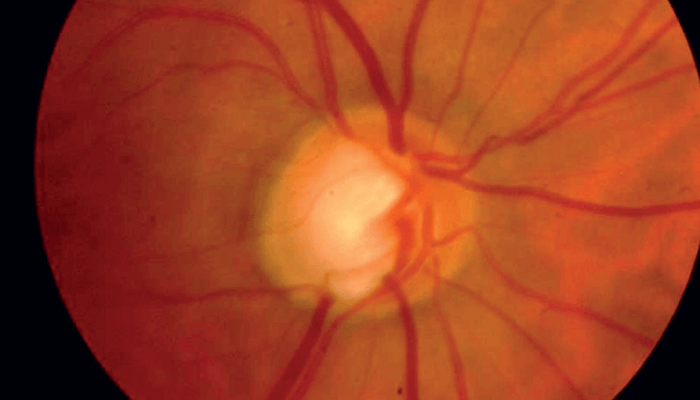

A 57-year-old Caucasian woman with a longstanding history of glaucoma and significant visual field loss in her right eye presented with treated intraocular pressures in the high teens. Her visual field in the right eye showed a deep superior paracentral defect close to fixation, and the left eye showed scattered defects but was grossly normal. Dilated fundus examination on the right eye revealed a cup to disc ratio (C/D) of 0.7 with an inferior notch, and on the left eye a C/D of 0.6 (see Figure 1).